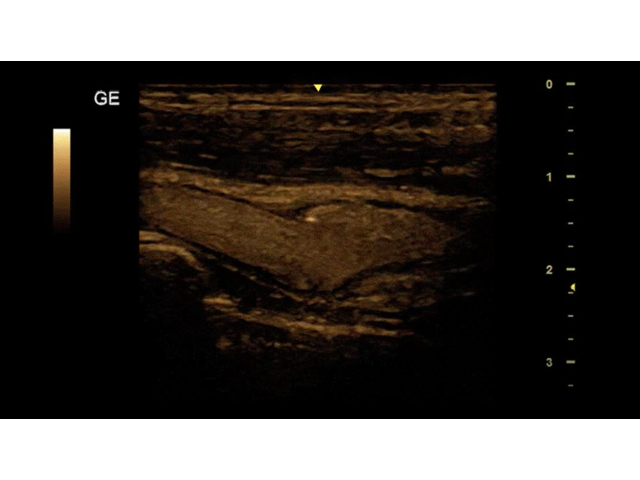

УЗИ-аппарат

GE Versana Essential

Ультразвуковой сканер GE Versana Essential отличается высокой точностью и мобильностью. Он широко используется при обследовании скелетно-мышечной системы и является незаменимым инструментом в урологии, гинекологии, педиатрии и общей радиологии.

Благодаря передовым технологиям и инновационным функциям, ультразвуковой сканер GE Versana Essential обеспечивает высокую четкость и детализацию получаемых изображений. Он позволяет врачам проводить диагностику и оценку состояния тканей и органов с высокой точностью, что способствует более точным и эффективным клиническим решениям.

• Линейный датчик GE L6-12-RS